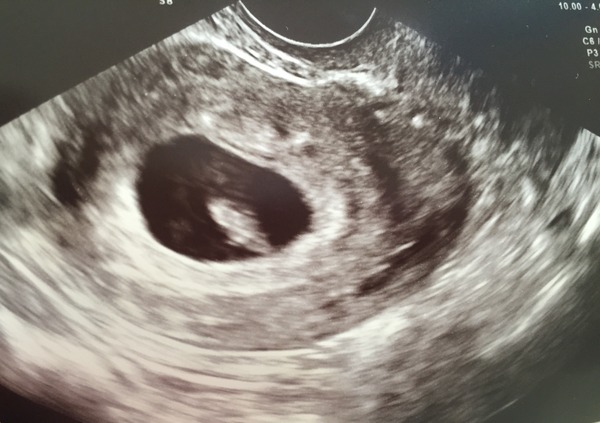

NoMontagues · 09/07/2015 14:02

Thanks guys! Here's the pic:

Oh and congrats to you too monk ! Smile

aww i can see an ickle nose montagues :) cute!